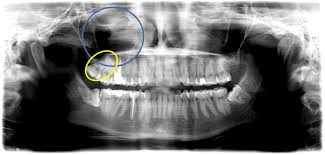

Von der Wuchsrichtung des Zahnes davon wie viel von dem jeweiligen Zahn bereits im Kiefer angelegt und verwachsen war und. Verläuft der Durchbruch der Weisheitszähne bei einigen Menschen ohne Komplikationen so leiden andere unter starken Schmerzen und Entzündungen die sich über mehrere Monate hinweg ziehen. Schmerzen nach dem Ziehen der Weisheitszähne.

Wie stark die Schmerzen sind und wie lange sie andauern hängt von einigen Faktoren ab. Dann allerdings sollten diese langsam abklingen. Bei den meisten Entfernungen der Weisheitszähne entstehen nur leichte Schmerzen oft hat man überhaupt keine.

Es dauert je nach der Größe des Weisheitszahns und sonstigen Faktoren recht lange bis die Wunde vollständig verheilt ist. Das durchschnittliche Alter in dem die Weisheitszähne durchbrechen beträgt etwa 16 Jahre. Es kann 7-14 Tage dauern bis sie vollständig abklingen.